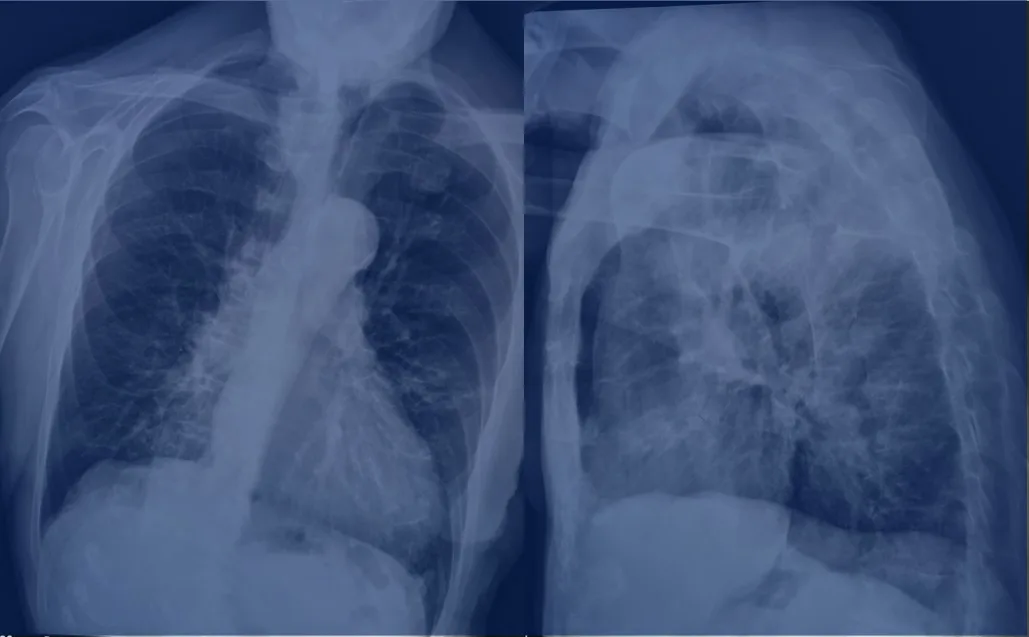

Nella malattia fisica, il processo anomalo ha come causa iniziale o provoca un difetto negli organi o in una funzione fisiologica: alcuni esempi sono il diabete, un cancro, la meningite.

2.2 Malattie croniche incurabili

La diagnosi di una malattia cronica, per la quale non è prevista alcuna cura, è motivo di preoccupazione che si accresce in proporzione alla gravità del quadro clinico. L’esistenza non sarà come prima, anche se solo a causa delle modifiche che bisognerà fare nello stile di vita: un piano di esercizi fisici, un’alimentazione particolare, dei farmaci, ecc. Se ci viene diagnosticato il diabete, dovremo seguire la dieta, magari usare l’insulina, fare frequenti test di controllo; in caso di ipertensione, problemi di colesterolo, insufficienza renale o cardiaca, dovremo ridurre il sale o i grassi, ecc.